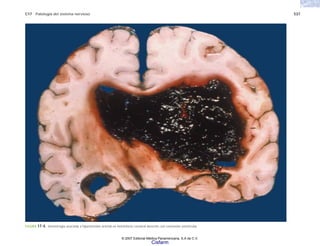

FIGURA 6-8. Meningitis aguda purulenta por neumococo. Espacio subaracnoideo ocupado por exudado con trombosis de las venas cerebrales corticales.